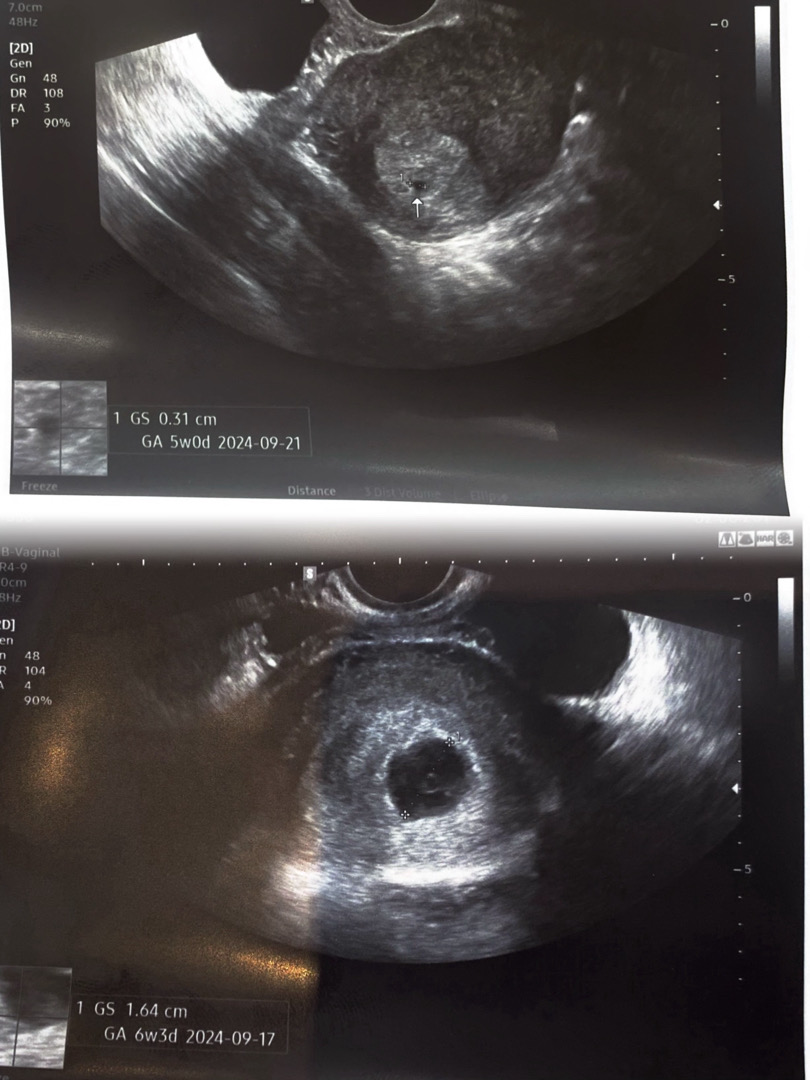

아기집 작았다가 갑자기 커짐ㅇ,ㅇ

1/20에 갔을 때 0.31cm라 너무 작나 싶었는데 1/26 오늘 가보니 1.64cm 되어 있더라구요 6일만에 이렇게 커질 수 있구나 싶어서 엄청 놀랐어요ㅋㅋ 아기집 너무 작다고 걱정마셔요~! 금방 커지네용!! 참고로 전 6일동안 복통만 있었어요! (생리통 느낌)